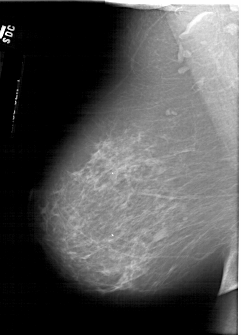

A_1618_1.LEFT_MLO

LEFT_MLO LINES 6031 PIXELS_PER_LINE 4321 BITS_PER_PIXEL 12 RESOLUTION 43.5 NON_OVERLAY